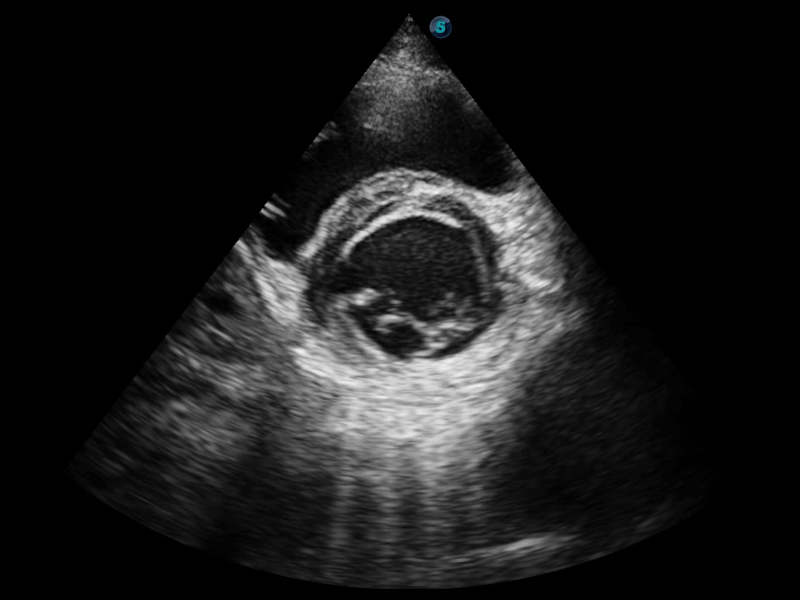

μ-Scan+新一代微米成像技术

新一代微米成像技术大大提高了器官和病变的可见性。高清对比度分辨率将抑制斑点噪声,同时保持真实的组织结构。

临床图像